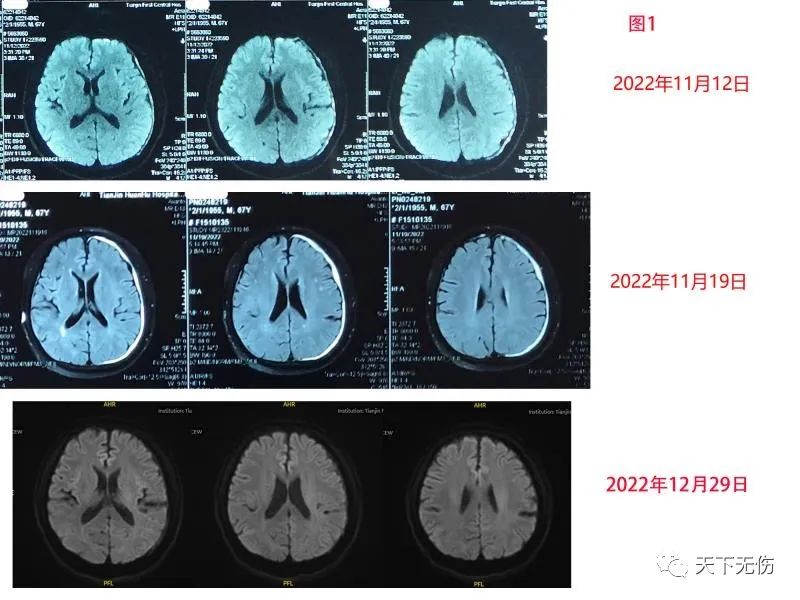

3例患者中还是包括了1例慢性硬膜下血肿的患者,延续了自2020年以来,我每次门诊都有慢性硬膜下血肿患者就诊的传统。这是1例无明显外伤的67岁男性患者,他只记得自己在发病前打过1次剧烈的喷嚏,在喷嚏过后,左眼胀痛。然后,他去天津某医院查头MRI发现有左侧薄层硬膜下血肿。那里的医生按照我们达成的共识,给患者口服阿托伐他汀钙和甘油果糖治疗,患者症状没有根本好转。于是他从线上找到我,于11月21日辗转来我门诊治疗,我为他调整了治疗方案后,他就“消失”了一个多月。这是他第二次来看我门诊,一来就告诉我他已经没有任何不适,说是吃了我的药仅3天症状就消失了。碍于疫情,一直没敢来医院复查。今天复查头MRI显示他的血肿几乎消失殆尽(图1)。化验检查没有发现明显异常,看患者情况很好,我决定给他停药。